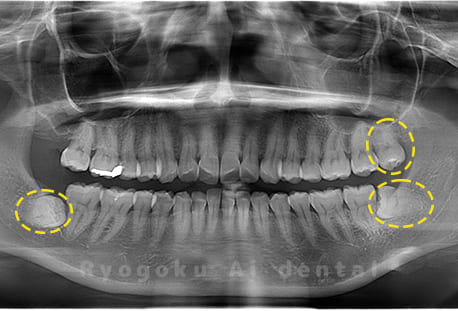

斜めに生えている親知らず

親知らずが斜めに生えて隣の歯にぶつかって圧迫してしまうタイプです。

このタイプが最も多いです。このタイプは虫歯になりやすいだけでなく、隣の歯を圧迫し、咬み合わせや歯並びに影響が出る場合もあるので抜歯をおすすめします。